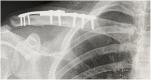

Case presentation: A 25-year-old male with previously (six years earlier) surgically treated clavicle fracture presented with a peri-implant clavicle fracture requiring surgical treatment. The management involved overlaying an implant to fix the lateral clavicle fracture without removing the previous plate. Complete bone healing was observed without any further complication.

Clinical discussion: Despite the low rate of implant failure in clavicle fractures, this complication occurs mainly in elderly patients with poor bone quality. No PIF have been described in the literature prior to this. This case report demonstrates a young patient with good bone quality and previous fracture fixation presenting with PIF which has now shown complete bone healing.

Conclusion: In this case, overlying an additional plate on the lateral clavicle portion without removing the previous plate increased the stability of the fracture. It demonstrates the value of overlaying plate osteosyntheses for patients with clavicle PIF.